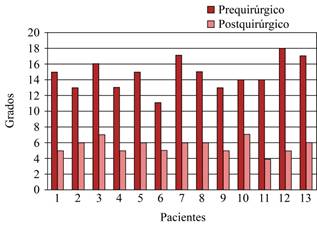

Radiográficamente, obtuvimos una angulación tibioastragalina en varo prequirúrgica de 14.6 (± 1.9) contra una angulación postquirúrgica a los seis meses de 5.6 (± 0.8) (Figuras 6, 7 y 8).

Diferentes procedimientos existen para la inestabilidad; sin embargo, la mayoría requiere grandes abordajes, comprometen al peroneo corto y a la biomecánica del pie.17 En comparación con otros procedimientos, éste permite respetar la movilidad subastragalina. Veintisiete pacientes con inestabilidad crónica fueron tratados con el procedimiento de Evans y seguidos durante un período de 10 años. Una restricción moderada en la inversión fue vista en nueve pacientes (34.61%), tres (11.5%) tuvieron un cajón anterior positivo y cinco (19.2%) presentaron cambios degenerativos.18 En un seguimiento de 18 años basado en la técnica de Chisman-Snook, 18% experimentó inestabilidad; es asociado con un alto riesgo de complicaciones comparado con la reparación anatómica.19 En nuestro estudio, ningún paciente experimentó inestabilidad residual y la movilidad subastragalina únicamente se vio alterada en uno (7.6%), al mostrar rigidez tras la reparación.

A dicho procedimiento, además, se añadió el uso de anclas para reforzar la reparación. Un estudio evaluó a 22 pacientes con inestabilidad crónica que fueron intervenidos utilizando anclas como parte del procedimiento de Broström. Hubo una media de 34.5 meses de seguimiento, 20 pacientes reportaron resultados excelentes y buenos valorados con escala de Karlsson y escala funcional de tobillo de Peterson. (p = 0.013).21 En nuestro estudio, valorados mediante la escala AOFAS a seis meses del procedimiento, mostraron mejoría para el dolor, alineación, movilidad subastragalina y estabilidad previamente mencionadas. Las radiografías con estrés en varo postquirúrgicas mostraron resultados satisfactorios. Demostraron una reducción de la angulación tibiastragalina en varo y con esto, la corrección de la inestabilidad prequirúrgica.

No quedaron tobillos inestables al valorarse clínica y radiográficamente. No hubo pacientes postoperados con prueba de cajón anterior o bostezo lateral positivo.